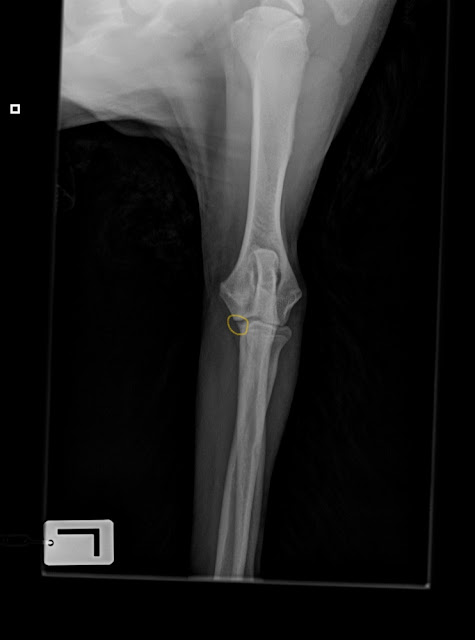

Soitin pariin paikkaan, ja niistä kerrottiin etteivät arvioi kasvavan koiran luustokuvia, koska niissä on vielä kasvulinjat auki eikä ole kuvien katsomisesta tarpeeksi kokemusta. No päästiin sitten Kalliolan eläinklinikalle aivan ihanalle Erikalle Johanssonille. Häntäkin etukäteen kehuttiin, että on kyllä todella ammattitaitoinen ja osaa ne kuvatkin katsoa. Otettiin kuvat olista, kyynäristä ja vasemmasta kyynärästä vielä edestäkin. Tuohon alempaan kuvaan ympyröin keltaisella sen kohdan, joka saattaa olla irti ja joka helposti kasvuiässä murtuu. Ja sitten ollaan siinä varislisäkkeen irtopala-tilanteessa, mikä esim. meidän Jeculla oli ja leikattiin. Josta syystä myös saatan olla hiukka enempi jännäkakka housussa tässä tilanteessa.

Höpillä oli kaikki onneksi luustossa ok, joten sen puoleen sai huokaista helpotuksesta. Puhuttiin ihan huvin vuoksi kaverin kanssa välikuvaamisesta, mitä mm. bordercollieiden omistajat tekevät usein. Noh, tulihan se sitten tehtyä vaikka vitsillä siitä puhuttiinkin. Nämä pentujen luustokuvat on kyllä hiukan jännittävän näköisiä, ekan kerran kun näin niin meinasi sydän pysähtyä, kun tosiaan eivät ole vielä luutuneet. Höpihän on nyt n. 7,5 kk vanha.